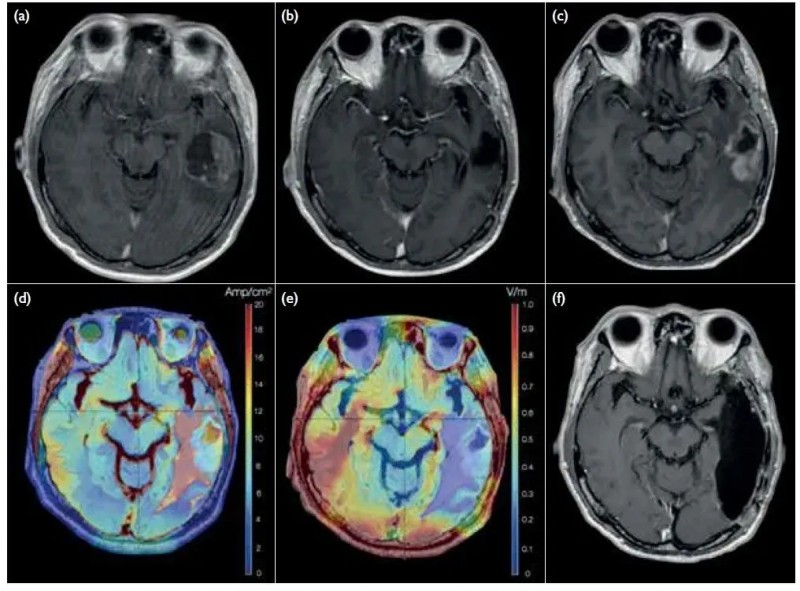

结果显示:治疗后,患者ECOG状态为1,生活质量良好,截至2022年已存活45个月(超3年),远高于传统治疗预估的15个月中位总生存期(下图展示了该患者电场疗法联合治疗前后的影像学对比图)。

▲图源“Hong Kong Med J”,版权归原作者所有,如无意中侵犯了知识产权,请联系我们删除